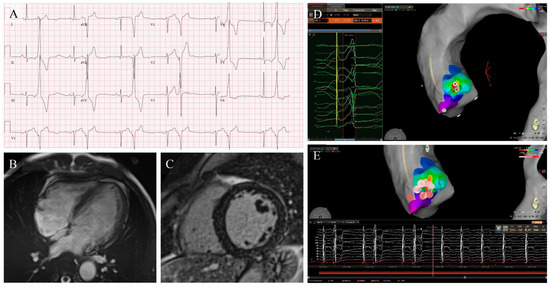

Premature Ventricular Complex-Induced Cardiomyopathy, a Review: Current Insights, Diagnostic Challenges, and Therapeutic Strategies

Premature Ventricular Complexes (PVCs) are among the most frequent ventricular arrhythmias observed in daily cardiology practice. Although often benign, sustained high ectopic activity can result in left ventricular dysfunction known as PVC-induced Cardiomyopathy (PVC-CMP), a condition that is frequently reversible when the arrhythmia [...] Read more.

Premature Ventricular Complexes (PVCs) are among the most frequent ventricular arrhythmias observed in daily cardiology practice. Although often benign, sustained high ectopic activity can result in left ventricular dysfunction known as PVC-induced Cardiomyopathy (PVC-CMP), a condition that is frequently reversible when the arrhythmia is effectively suppressed. The underlying mechanisms are multifaceted, involving electromechanical dyssynchrony, contractile inefficiency, abnormal calcium cycling, neurohormonal activation, and progressive structural remodeling. The likelihood of developing PVC-CMP varies among individuals and is influenced by electrophysiological and structural factors. Diagnosis relies on prolonged rhythm monitoring, comprehensive multimodality imaging, and demonstration of ventricular recovery after reducing the ectopic burden, which, in turn, confirms causality. Over the past decade, major advances in electrocardiographic mapping, cardiac imaging, and ablation therapy have transformed this field, demonstrating excellent efficacy and safety profiles. In parallel, artificial intelligence and computational mapping are emerging as powerful tools for prediction and procedural guidance. Recognition of PVC-CMP as a distinct, treatable cardiomyopathy highlights the importance of early detection and individualized therapy, offering the prospect of complete functional recovery and the prevention of heart failure progression. Full article

Figure 1